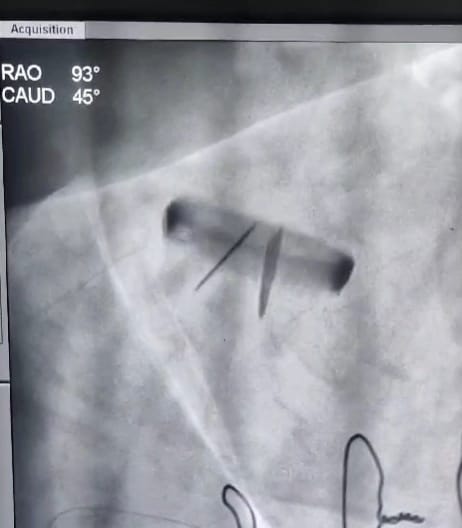

• Percutaneous valvuloplasty procedures